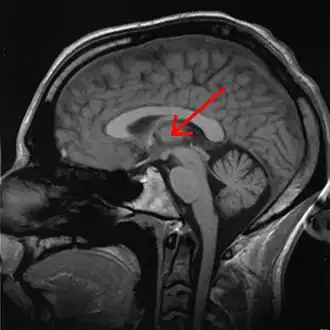

![]() Thalamus marked (MRI cross-section) | |

The thalamus (pl.: thalami; from Greek θάλαμος, "chamber") is a large mass of gray matter on the lateral wall of the third ventricle forming the dorsal part of the diencephalon (a division of the forebrain). Nerve fibers project out of the thalamus to the cerebral cortex in all directions, known as the thalamocortical radiations, allowing hub-like exchanges of information. It has several functions, such as the relaying of sensory and motor signals to the cerebral cortex[1][2] and the regulation of consciousness, sleep, and alertness.[3][4]

Anatomically, the thalami are paramedian symmetrical structures (left and right), within the vertebrate brain, situated between the cerebral cortex and the midbrain. It forms during embryonic development as the main product of the diencephalon, as first recognized by the Swiss embryologist and anatomist Wilhelm His Sr. in 1893.[5]

The thalami are paired structures of gray matter about four centimetres long and ovoid in appearance,[6] located in the forebrain which is superior to the midbrain, near the center of the brain with nerve fibers projecting out to the cerebral cortex in all directions. In fact, almost all thalamic neurons (with the notable exception of the thalamic reticular nucleus[7]) project to the cerebral cortex, and every region of the cortex so far studied has been found to innervate the thalamus.[8]